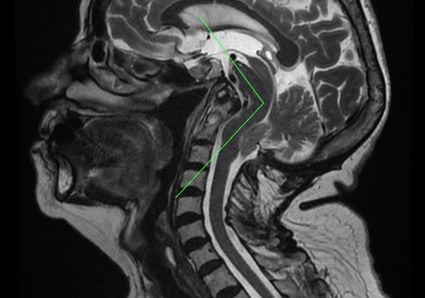

圖1- 顱頸部矢狀磁共振影像 – 可見脊髓腦橋水平的腦幹角度(腦幹扭結症)、顱底凹陷、齒狀突畸形和小腦扁桃體下疝。另外,值得強調一提的是小腦上方明顯可見的空間,圖中驗證了終絲牽扯的理論並同時推翻後顱窩空間不足造成下疝的理論。

腦幹扭結症(Angulation of the Brainstem)是腦橋和脊髓之間角度的變異,患者常伴隨扁平顱底、顱底凹陷和齒狀突畸形。此外,它也常和小腦扁桃體下疝一同出現。根據終絲系統®研究,腦幹扭結症的病因與後顱窩骨性畸形有很大關聯,是為了緩和脊髓牽扯對身體發育造成影響而形成的。

腦幹扭結症是一種先天性的變異,是由於胎兒在胚胎生長期時,脊髓與脊柱中樞神經系統發展不協調所造成。脊髓脊柱發展不協調造成了終絲異常的對脊髓的牽引力,其力量從尾骨傳遞到脊髓、顱骨和大腦。顱骨與大腦的畸形決定了神經角度的形狀和強度。當終絲牽扯力越強,腦橋和脊髓之間角度的變異也會越大。